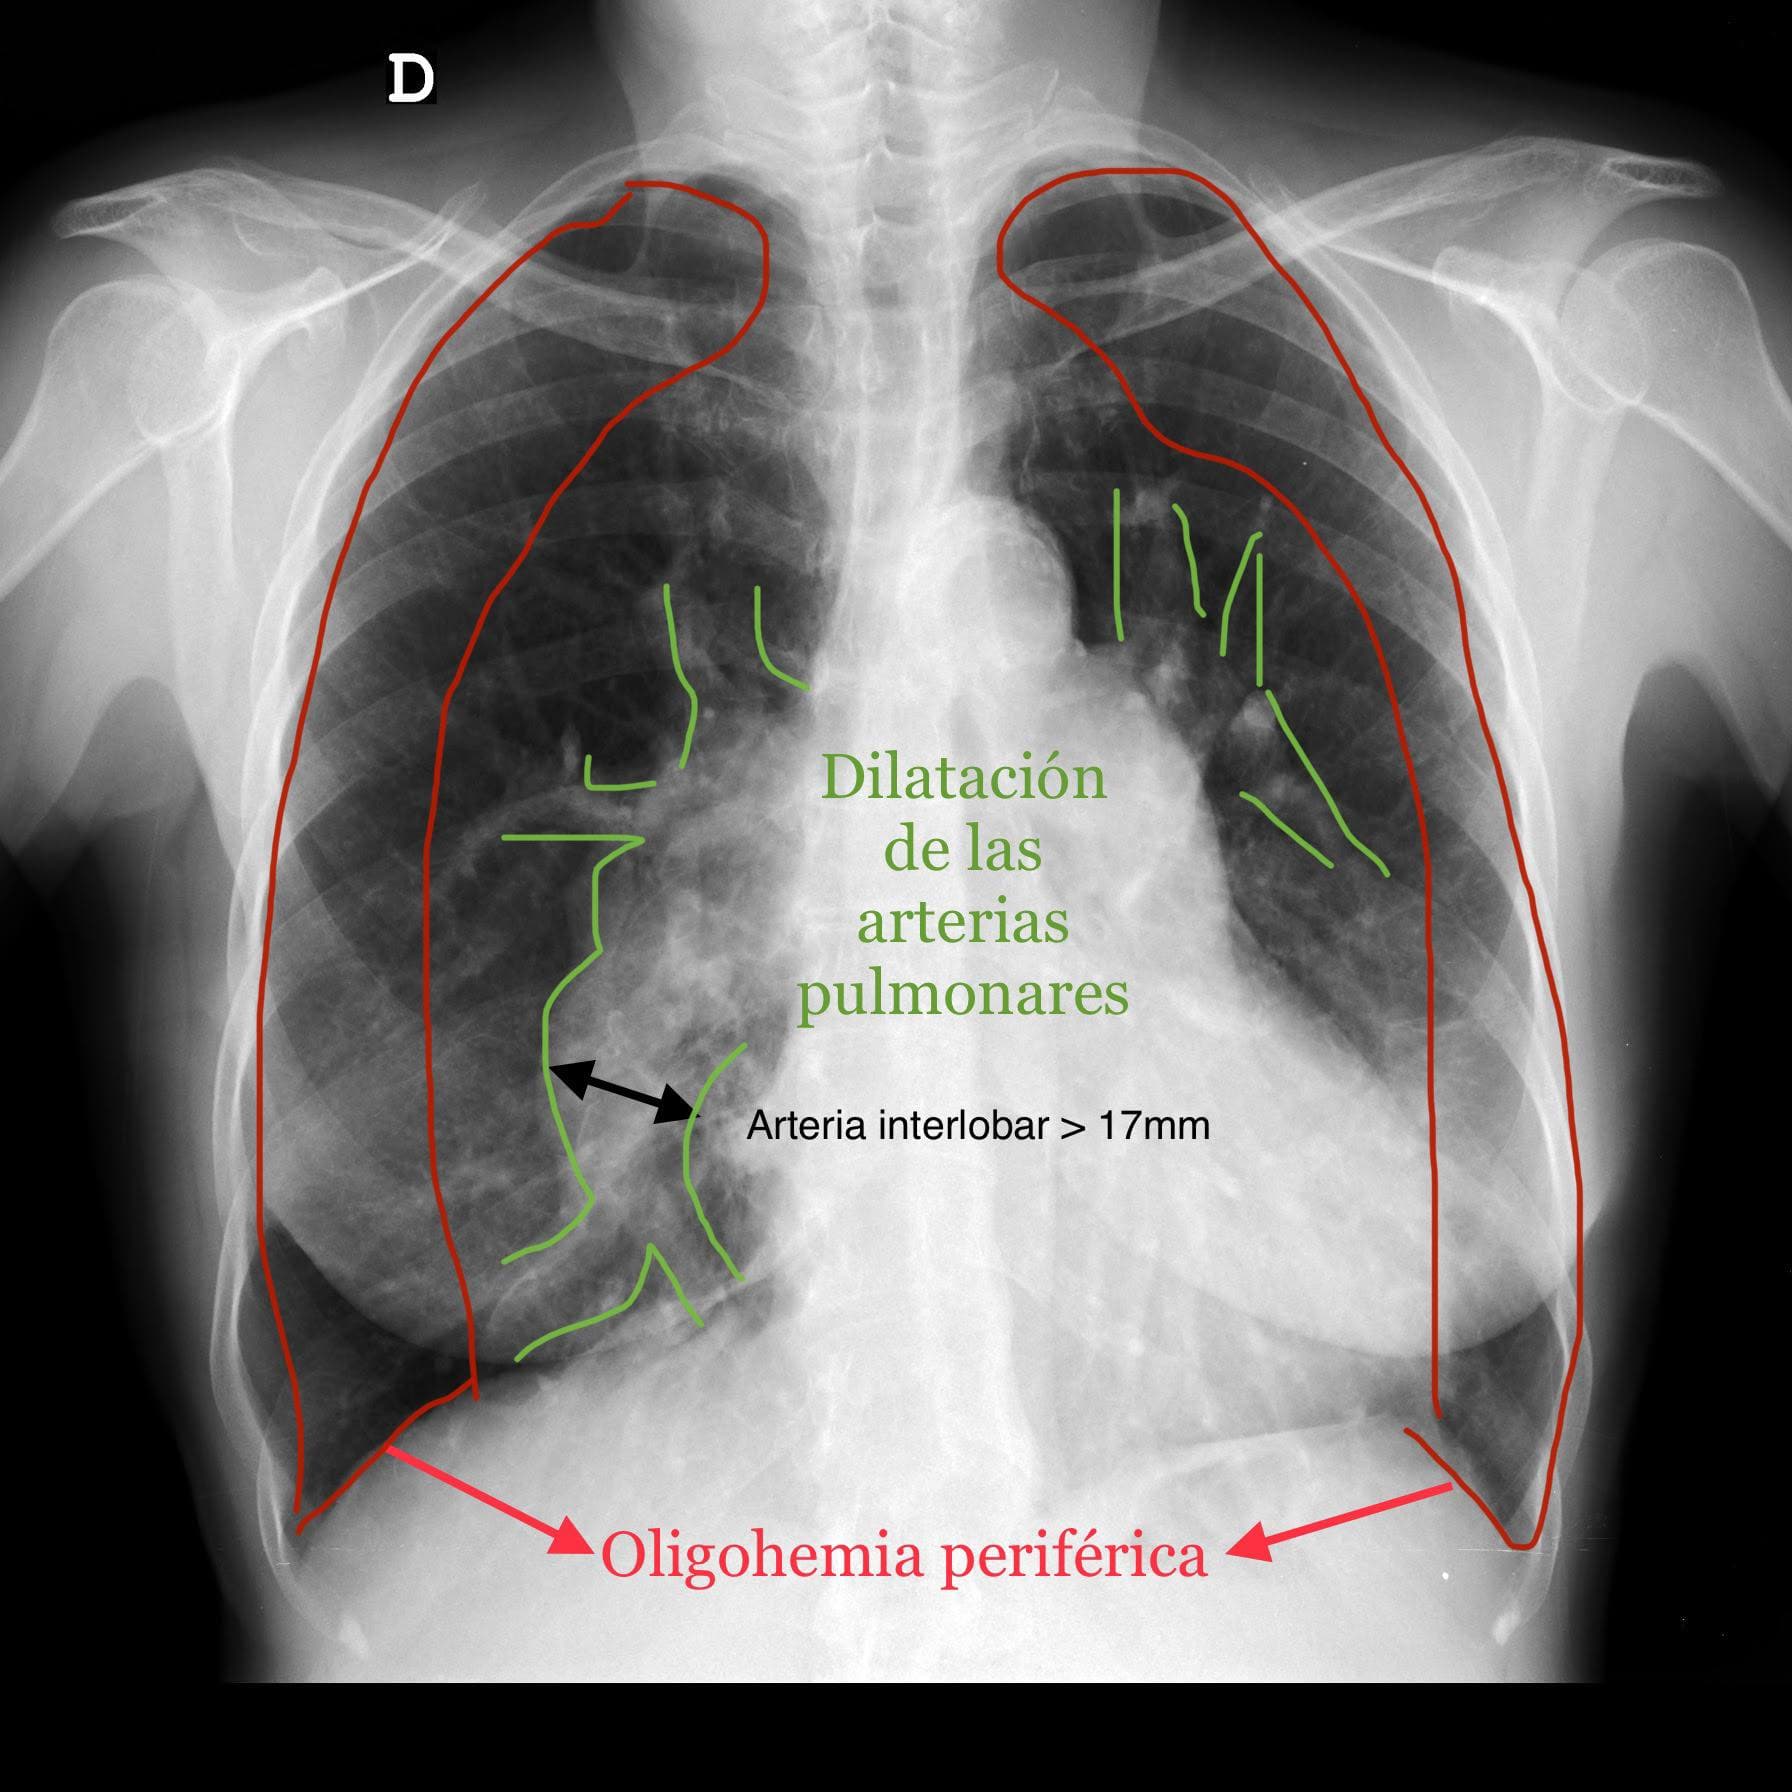

Rayos X y radiografías panorámicas

Evaluación de huesos, tórax y articulaciones, escoliosis. El primer paso en el diagnóstico, listo en minutos.